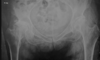

Masculino, 12 anos

Síndrome da sincondrose isquiopúbica assimétrica (Doença de Van Neck-Odelberg)

Variante da normalidade (em geral assintomático)

Crianças

Alargamento e radioluscência na sincondrose isquiopúbica, que simula neoplasias, infecção;